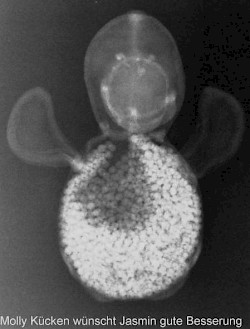

Erst das Kuscheltier - dann das Kind

Kinder kommen oft sehr ängstlich mit Kuscheltieren oder Puppen zum Röntgen. Um den Kindern diese Angst zu nehmen, kann man vor deren neugierigen Augen, zuerst die kuscheligen Begleiter unter die Röhre legen.

Spätestens wenn die Kinder die Bilder Ihrer Kuscheltiere sehen ist die Angst vorm Röntgen meist vergessen. So wie bei den unten abgebildeten Bildern.